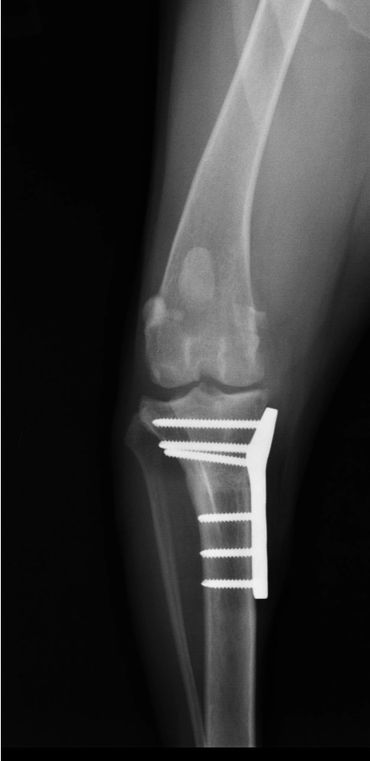

If your pet has a torn CCL they will usually be uncomfortable and manifest this as limping. They often prefer to limit their own activity level due to the pain and may be more sedentary. When a CCL tear is diagnosed, usually the best option is to stabilize the stifle surgically for the best outcome. One technique commonly performed for decades has been the Tibial Plateau Leveling Osteotomy (TPLO). The TPLO was designed to eliminate the tibial thrust motion that occurs with a CCL tear and thus return stability to the stifle for return to function. The TPLO procedure is very technical and thus is best performed by experienced surgeons. Initially the TPLO was only taught by the original designer of the procedure, Slocum Enterprises, and luckily Dr. House managed to complete this training program before it ended. To perform a TPLO procedure a bone cut (osteotomy) is made in the shin bone (tibia) near the knee. This cut is curved and allows a change in the angle within the stifle to alter the forces as mentioned above. Once the cut is made and the bone is rotated, a metal plate and screws are placed to hold the bone in its new position while it heals. These implants are usually left in place for life and are only removed if a reaction or infection should develop, which is generally uncommon. Since a cut is made in the bone for this procedure, patients must go through a rest period while the bone heals adequately for normal activity again. It is critical that patients rest to avoid breaking their bone or the implants. The post-operative instructions typically followed are below. If your pet has been diagnosed with a CCL tear, a TPLO may be recommended. This procedure is usually best performed in pets weighing 50 pounds and above. It can be performed in animals under 50 pounds, however, and this can be determined at a surgical consultation. Dr. House performs the TPLO procedure almost daily and would be happy to meet with you and your pet to discuss and perform the procedure accordingly at your local veterinary clinic.

At 8 weeks following surgery, your pet should return to their vet for x-rays. The x-rays are done to assess the bone healing process and to ensure the implants placed have remained unchanged. Your pet's ambulation will also be assessed to ensure healing is occurring as expected. Once this visit is completed, and your pet is doing well, you may then start increasing your leash walks duration and frequency for 4 additional weeks. By the 12 week timepoint after surgery, your pet's bone should be adequately healed to run and play like they used to! Remember that following the recovery process strictly is critical to healing well and that each patient may heal differently. If you ever have concerns about the recovery of your pet, please don't hesitate to ask. We all want your pet to heal well from their surgery and be happy and healthy again!